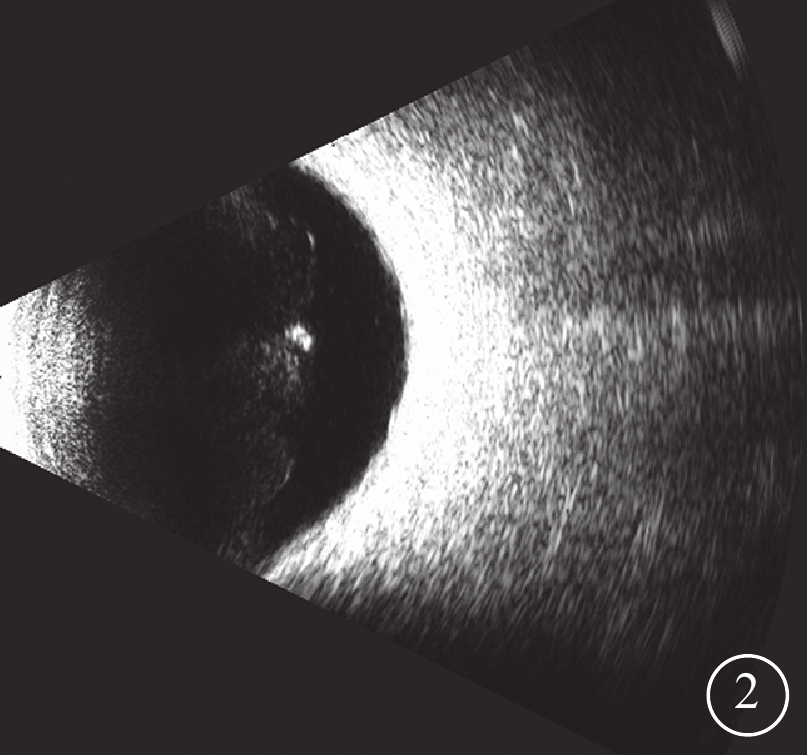

明確診斷后,給予患者右眼玻璃體腔注射更昔洛韋0.1 ml(含更昔洛韋400 μg)1次,其后患者拒絕定期玻璃體腔注射更昔洛韋。未行眼底病灶激光光凝以及全身抗病毒治療。器官移植科會診結果,調整他克莫司用藥劑量,維持他克莫司濃度為6 pg/ml。3個月后復查,患者主訴右眼眼前黑影消失,BCVA 1.0。房水CMV病毒載量降至0;血CMV-DNA低于最低檢出限。隨訪期間,患者右眼顳上方白色病灶逐漸消退(圖1B,1C)。1年后,患者主訴右眼飛蚊癥明顯,眼底復查無明顯異常。B型超聲檢查,右眼玻璃體嚴重混濁(圖2)。血他克莫司濃度于5~6 pg/ml穩定波動。對患者進行密切隨訪,至2021年3月右眼眼底情況穩定,未出現視網膜脫離等并發癥。